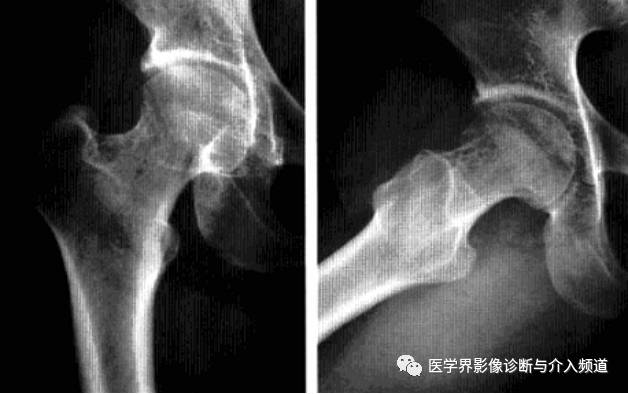

髋关节撞击综合征

也称股骨髋臼撞击综合征,是由于股骨近端和髋臼盂缘间解剖的异常,或解剖正常但长期不正常外力作用于髋关节,导致两者长期不正常接触、碰撞,产生反复的微型创伤致使关节盂缘和关节软骨退变,从而引起慢性髋关节疼痛及髋关节屈曲和内收受限的疾病。分为凸轮撞击和钳夹撞击两个类型。

影像诊断:X线平片是基本检查方法,直立骨盆正位及髋关节侧位片。

平片:①凸轮撞击型,正位片示头颈连接处扁平,呈“左轮枪柄”样畸形,侧位片示股骨头颈凹陷减少,中心边缘角变小<16度,②钳夹撞击型,髋臼窝过深,髋臼后倾,呈相交8字征,偏心距缩短<9mm。

CT:三维CT可测量股骨头颈连接处前外侧偏移量减低,股骨头颈联合处前上缘可见骨性突起。

MRI:股骨头颈凹陷减少(α>50°),股骨颈宽度与股骨头半径比率增大,髋臼后倾。盂缘退行性改变,撕裂、囊肿,关节间隙后期出现狭窄,周围肌肉炎症。